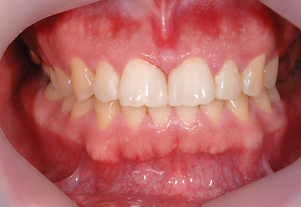

症例1

Before

After

- POINT

- 20代前半の患者様です。年齢が若くても歯周病、歯肉炎は発症してしまいます。ホームケアの指導と治療の説明をしっかり行い、専門家によって丁寧に歯石を除去することで、健康な歯茎を取り戻しました。前歯の厚い歯茎は歯茎の形態を整える手術をしています。すべて保険治療です。